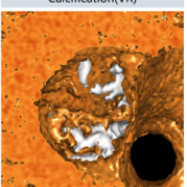

主动脉CT

瓣膜形态

入路状况

结构上,该病例为Type0型二叶瓣,瓣叶钙化、增厚严重,且流出道呈喇叭口型。考虑远期效果,为避免瓣膜选择过大打开不良造成瓣膜过早衰败,可参照瓣上狭窄结构Downsize选择TAV24瓣膜;同时为了避免瓣膜移位及瓣周漏,应采取高位定位释放的策略,释放过程中应留意输送系统及导丝的牵拉稳定瓣膜位置,如遇瓣膜位置不佳,及时应用可回收功能进行再次定位释放。双侧入路直径充足,但双侧股动脉分叉均较高,可考虑主入路外科切开后于稍高处穿刺。